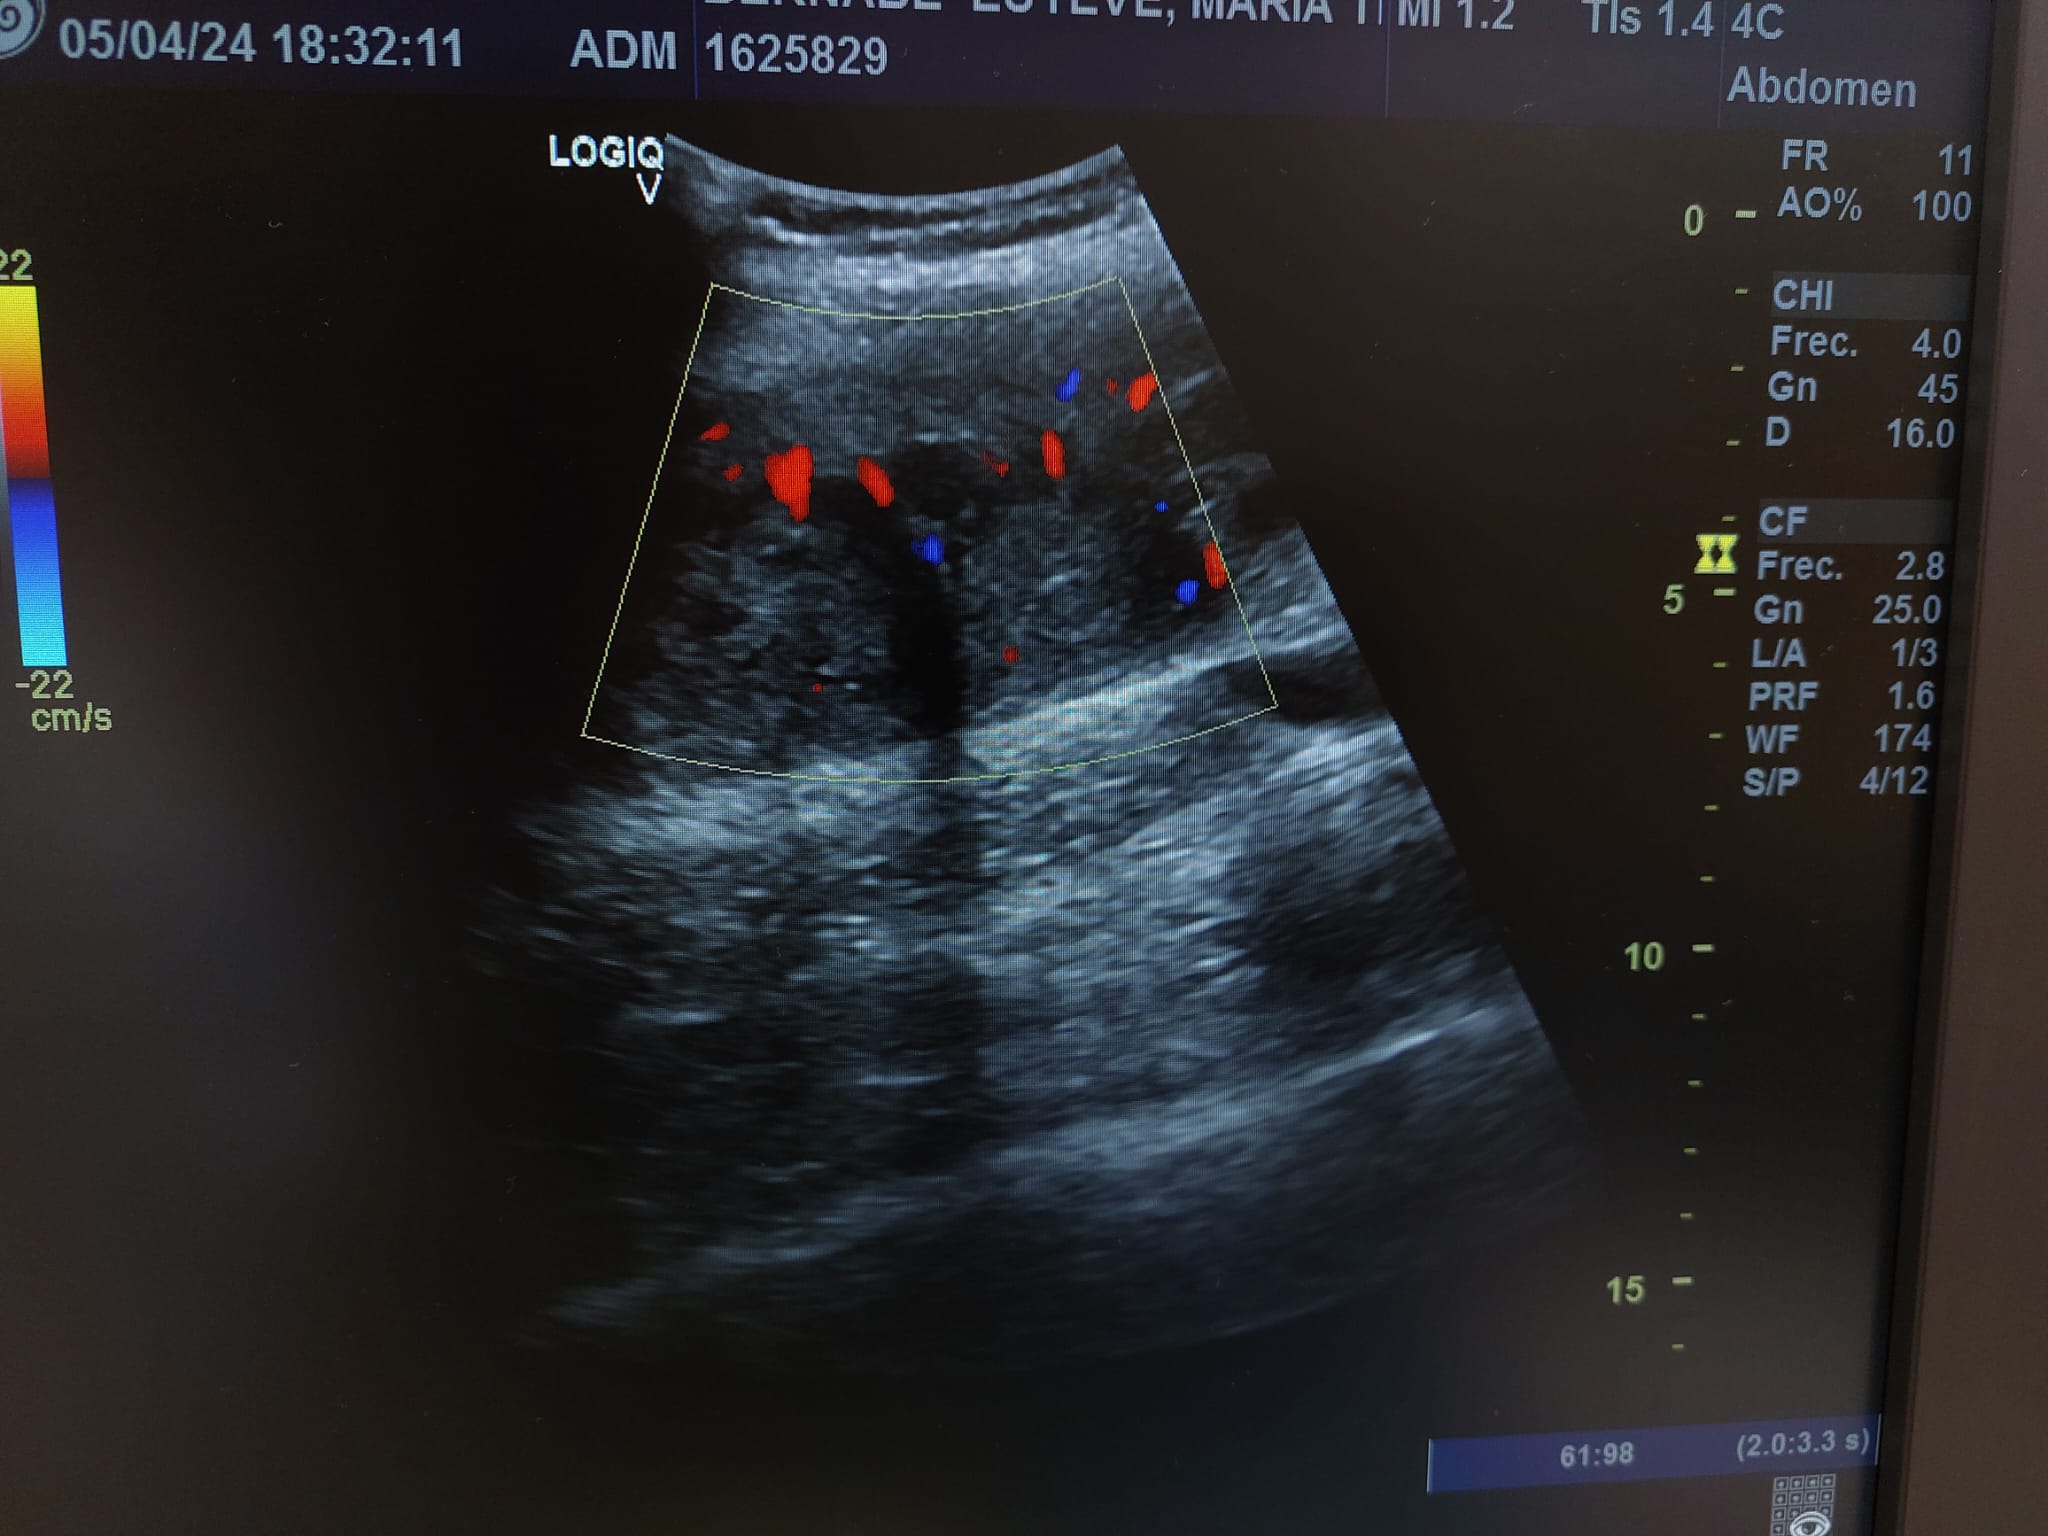

En el seguimiento se observa evolución tórpida sin mejoría clínica y en la ecografía de control se observa aumento notable de tamaño respecto al previo, estructura heterogénea de imagen anecoica con septos internos. Se aprecia edema intramuscular perilesional y captación al activar el Doppler. Se plantea la posibilidad de un hematoma sobreinfectado o, debido a su importante crecimiento, una probable etiología neoplásica. Tras hallazgos descritos en consulta, COT solicita de forma urgente la realización de RNM y biopsia de la lesión. Posteriormente, el resultado de las pruebas complementarias confirman diagnóstico de sarcoma histiocítico.